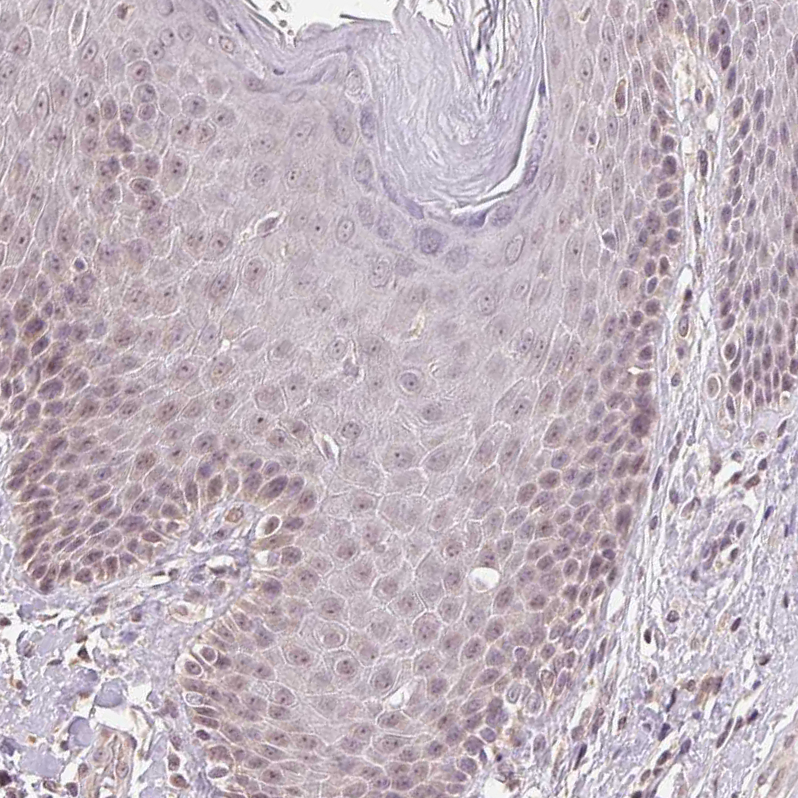

Immunohistochemistry analysis in human cerebral cortex and tonsil tissues using HPA034743 antibody. Corresponding PLCB1 RNA-seq data are presented for the same tissues.